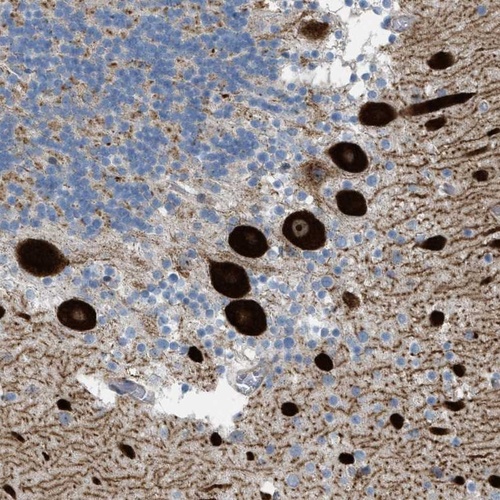

Immunohistochemical staining of human cerebellum shows strong nucleolar and cytoplasmic positivity in purkinje cells.